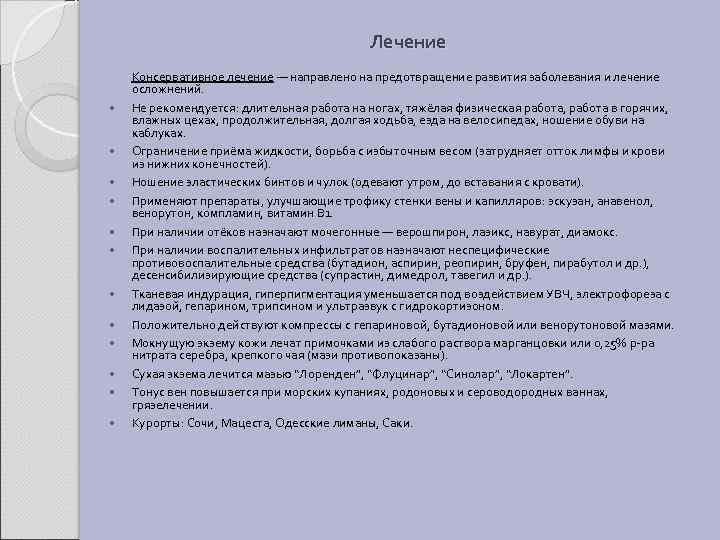

Лечение Консервативное лечение — направлено на предотвращение развития заболевания и лечение осложнений. Не рекомендуется: длительная работа на ногах, тяжёлая физическая работа, работа в горячих, влажных цехах, продолжительная, долгая ходьба, езда на велосипедах, ношение обуви на каблуках. Ограничение приёма жидкости, борьба с избыточным весом (затрудняет отток лимфы и крови из нижних конечностей). Ношение эластических бинтов и чулок (одевают утром, до вставания с кровати). Применяют препараты, улучшающие трофику стенки вены и капилляров: эскузан, анавенол, венорутон, компламин, витамин В 1. При наличии отёков назначают мочегонные — верошпирон, лазикс, навурат, диамокс. При наличии воспалительных инфильтратов назначают неспецифические противовоспалительные средства (бутадион, аспирин, реопирин, бруфен, пирабутол и др. ), десенсибилизирующие средства (супрастин, димедрол, тавегил и др. ). Тканевая индурация, гиперпигментация уменьшается под воздействием УВЧ, электрофореза с лидазой, гепарином, трипсином и ультразвук с гидрокортизоном. Положительно действуют компрессы с гепариновой, бутадионовой или венорутоновой мазями. Мокнущую экзему кожи лечат примочками из слабого раствора марганцовки или 0, 25% р-ра нитрата серебра, крепкого чая (мази противопоказаны). Сухая экзема лечится мазью “Лоренден”, “Флуцинар”, “Синолар”, “Локартен”. Тонус вен повышается при морских купаниях, родоновых и сероводородных ваннах, грязелечении. Курорты: Сочи, Мацеста, Одесские лиманы, Саки.